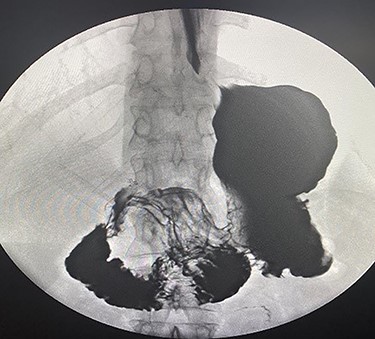

The patient taken to the operating room for diagnostic laparoscopy and proceed, after insufflating the abdomen the whole abdomen examined and showed proximal dilatation of small intestine with collapse of distal part of jejunum, the ileocecal junction identified and the small bowel examined proximally till the obstruction identified, which is fibrous band originating from the stomach to the proximal part of jejunum (Fig. 3), examination of this band showed that this band is caused by suture penetrating the stomach wall, which is going with the previous history of the endoscopic gastroplasty, reduction of the internal hernia done by releasing of the fibrous band, the herniated segment was healthy (Fig. 4).